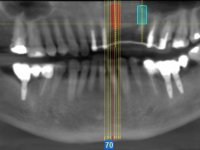

66-year-old male patient, non-smoker. It featured a 5-member metal-ceramic bridge with extreme mobility. Teeth 11 and 21 had infiltrated cervical margins. Both arches showed root exposure with signs of cervical abrasion. Composite resin “slots” were visible on the buccal surfaces of some mandibular teeth compatible with an orthodontic treatment with aligners that the patient was undergoing. After the imaging examination, it was found that the bridge's distal support, tooth 24, was irretrievably lost. The mesial pillars 11 and 21 had endodontic treatment and intraradicular posts. Teeth 25 and 26 also had endodontic treatment and extensive restorations in composite resin. In the lower jaw, two bridges were visible. In the third quadrant a 4-element bridge supported on tooth 35 and on 2 implants placed in the location of teeth 36 and 37. In the fourth quadrant a 3-element bridge supported on tooth 45 and an implant placed in the location of tooth 46. The patient presented a thick gingival phenotype and very good oral hygiene.

The patient was proposed to undergo a fixed oral rehabilitation consisting of a 2-element bridge over teeth 11 and 21 and a 5-element bridge over 3 implants that would be placed in the location of teeth 22, 24 and 26. The prosthetic structures would have an infrastructure in Zr coated with ceramic and the bridge over the implants would be screwed. The indicated extraction of teeth 25 and 26 and placement of an implant in the 26 site would imply surgery to fill the maxillary sinus. As the patient showed interest in having fixed temporary rehabilitation during treatment, we divided the treatment into 6 phases to achieve this goal: 1- Placement of a temporary bridge over teeth 11,21,25 and 26. With tooth extraction 24. 2- Placement of 2 implants in the location of teeth 22 and 24. 3- Placement of a temporary 6-element bridge over teeth 11 and 21 and over the implants. 4- Carrying out surgery to fill the maxillary sinus. 5 – Placement of the implant in the location of tooth 26 and in the area where the filling of the maxillary sinus was made. 6 – Placement of the definitive work.